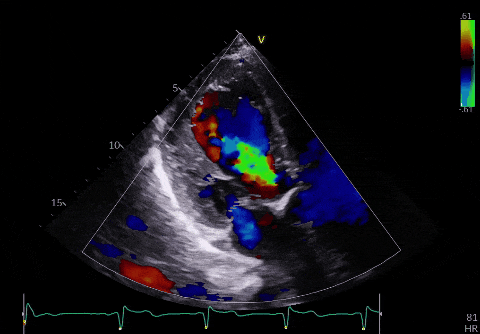

▲术后超声

原本严重的主动脉瓣反流瞬间消失,心脏的血流动力学立刻恢复正常。整个手术仅用时1小时,患者全程生命体征平稳,无任何并发症。